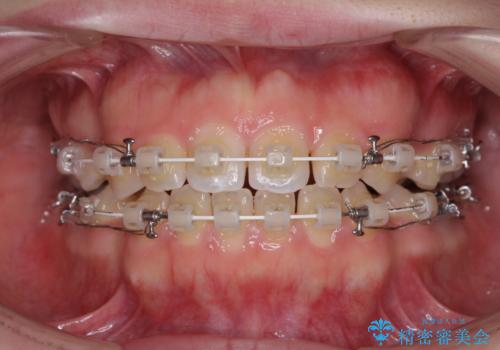

- 矯正装置

- 審美装置

治療は順調に進み、予定された期間で終了することができました。